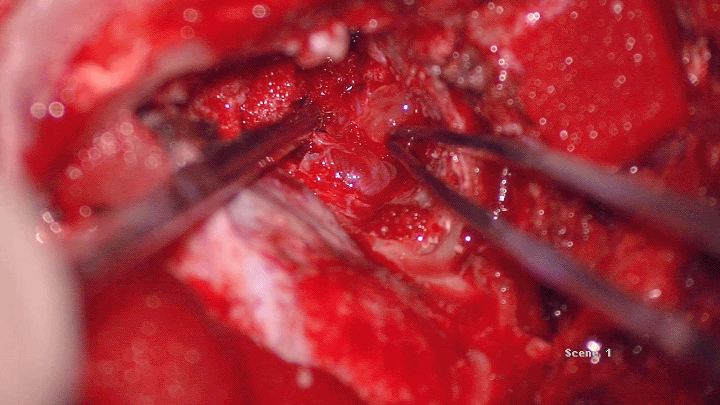

术中

尽可能沿肿瘤外包膜切除⏬

肿瘤呈半透明胶冻状⏬

全切后冲洗瘤腔⏬